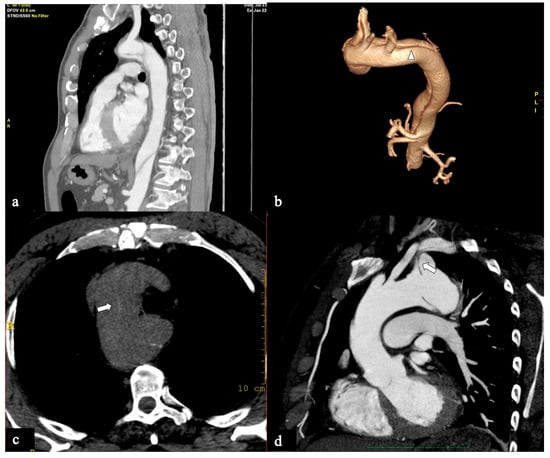

- In Configuration 2, the primary ET is situated within the aortic arch, and the dissection flap is confined solely to the arch (Arch alone). the primary ET is located in the aortic arch and the dissection flap is limited to the arch (Arch alone). This very uncommon configuration occurred in 4 (11%) patients (Figure 4) and is a very rare clinical entity. Configuration 2 is similar to the “group B” definition provided half of a century earlier by Dubost and colleagues [36], reported by Pasic in 1999 [37], and again proposed by Urbanski in 2016 [26]. An amount of 2/4 of these Arch alone patients received continued medical management with close imaging surveillance, and one- and two-year follow-up CTA examinations showed no dissection progression; 2/4 patients underwent hybrid or open surgical repair, one due to persisting pain, and the other one for cerebral malperfusion on follow-up CT.

- In Configuration 3 (Arch entry), the primary ET is situated within the aortic arch, and the flap extends into the DTA without affecting the ascending aorta [38]. This Configuration 3 occurred in 7 (19%) patients (Figure 5a,b). This AD configuration was already described as proximal type B dissection according to 2010 AHA guidelines [7] and recently reported as arch B group AD from IRAD [38] and as non-A non-B acute AD with entry tear in the aortic arch [39,40]. In this configuration, the ET was often located in the greater curvature of the arch (4/6), while in one case (1/7) its location was not clearly identified. In total, 4/7 of these patients underwent hybrid and 2/7 surgical therapy.